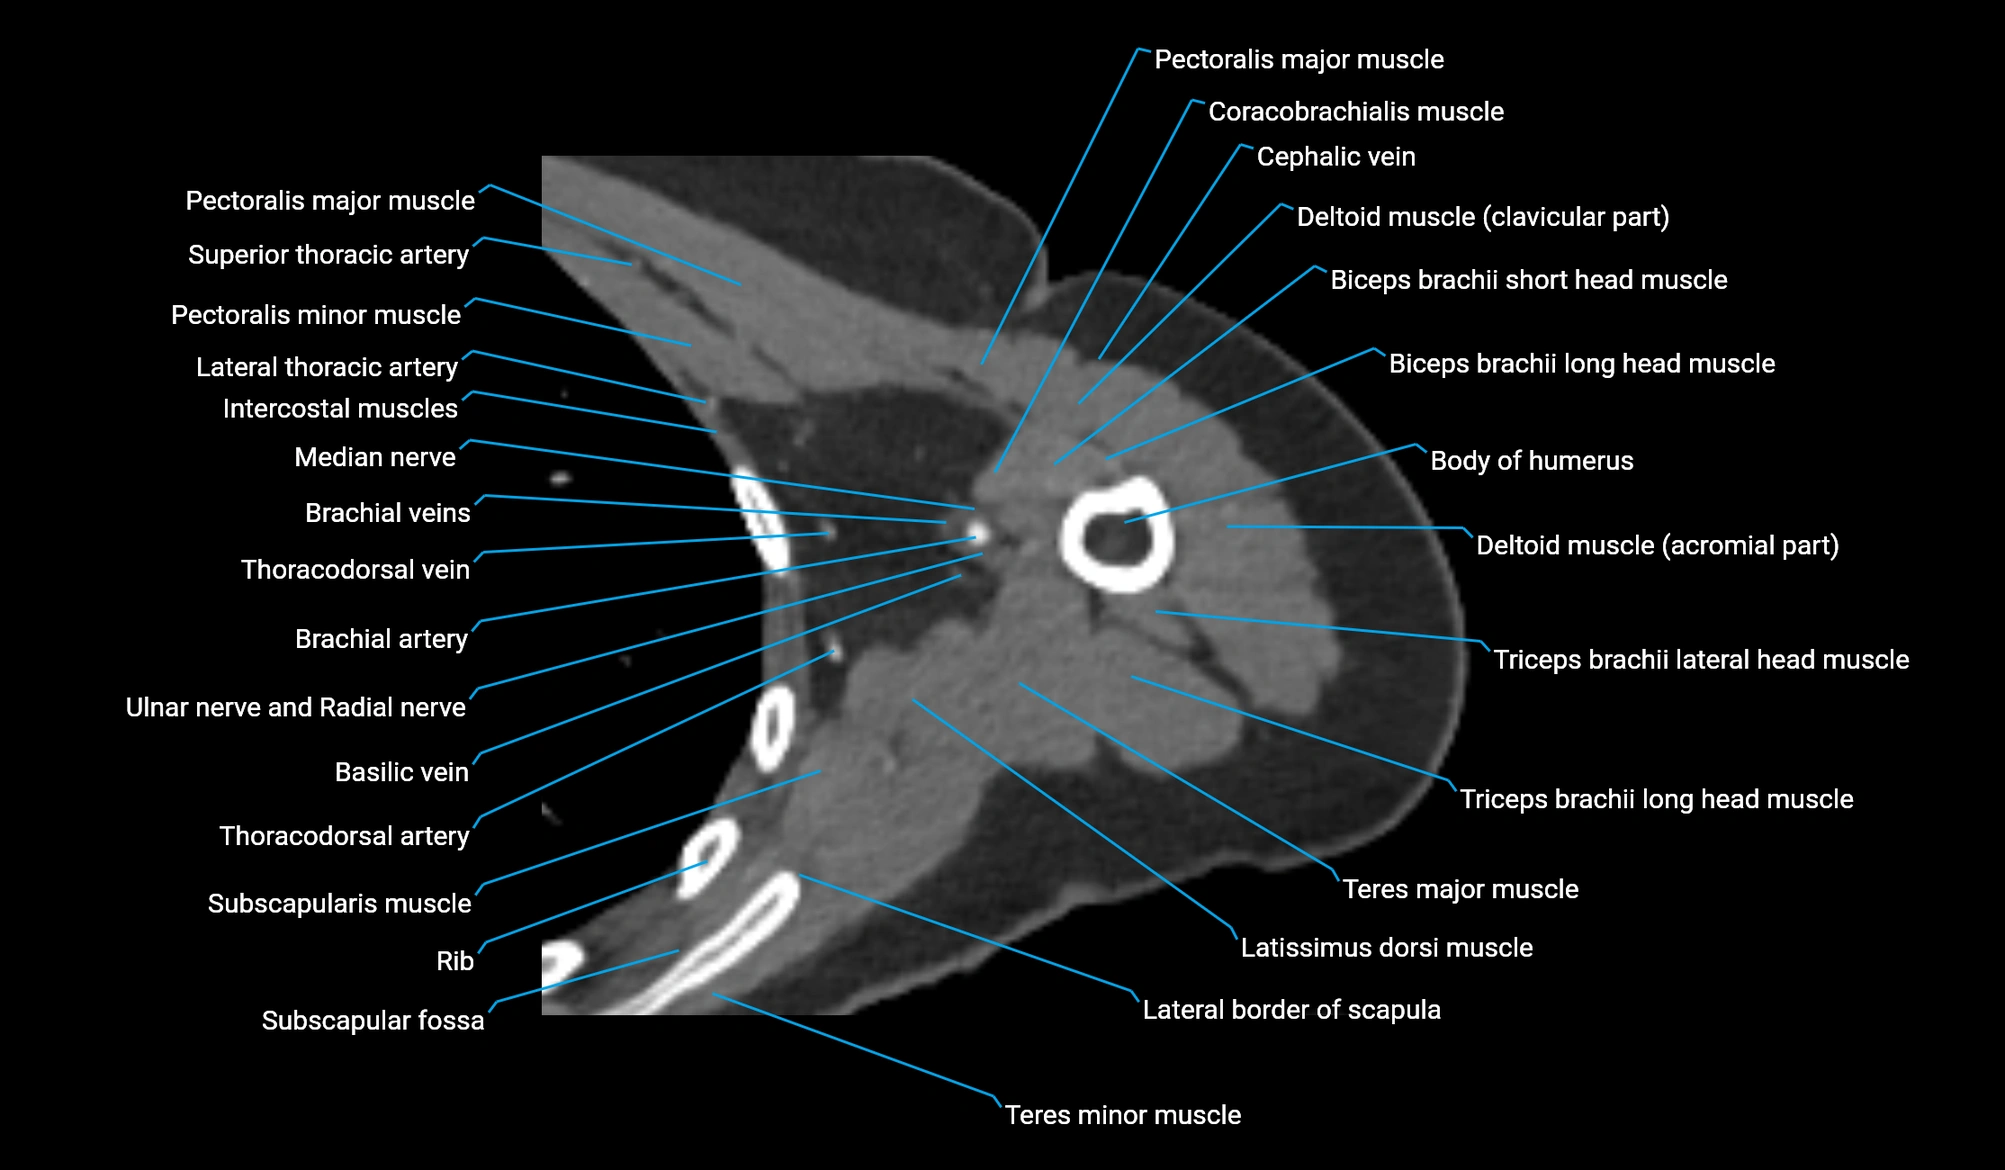

- Body of humerus

- Brachial artery

- Cephalic vein

- Coracobrachialis muscle

- Pectoralis major muscle

- Pectoralis minor muscle

- Teres major muscle

- Teres minor muscle

- Thoracodorsal artery